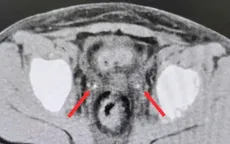

Phẫu thuật sỏi san hô phức tạp thành công cho bệnh nhân suy thận

VTV.vn - Bệnh viện Đại học Y Dược Shing Mark (Đồng Nai) vừa phẫu thuật thành công sỏi san hô 4x6 cm cho bệnh nhân suy thận, bằng kỹ thuật tán sỏi qua da đường hầm nhỏ.